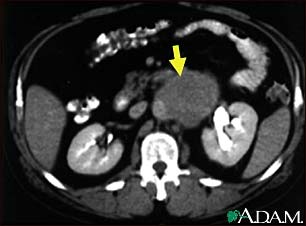

Lymph node metastases, CT scan

A CT scan of the middle abdomen showing a large tumor mass due to metastasis (spreading cancer) in abdominal lymph nodes.